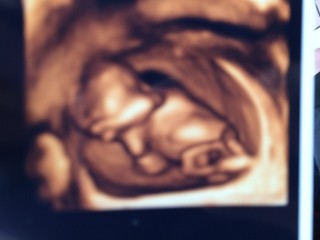

お尻をフリフリし始め、伸びや指しゃぶりをする姿に感激☆彡

9週の頃と比べると手足が屈折出来る程長くなり、脳や背骨もはっきりとわかり、随分人間らしくなりました。